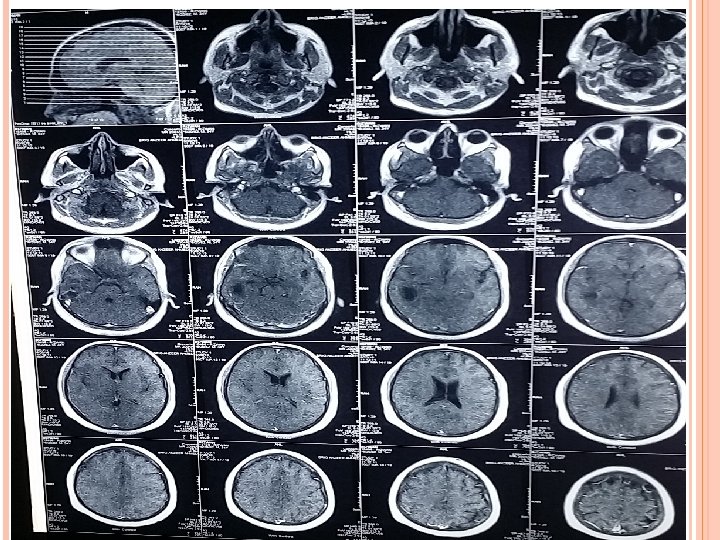

INVESTIGATIONS Blood Tests CBC (TLC-12000/u. L) CRP (3. 2 mg/L) ESR (28 mm/hr). Imaging CT scan Brain ( plain ) CT scan Brain with contrast. MRI Brain with contrast.

CT SCAN BRAIN WITH CONTRAST ( AFTER 1 WEEK)